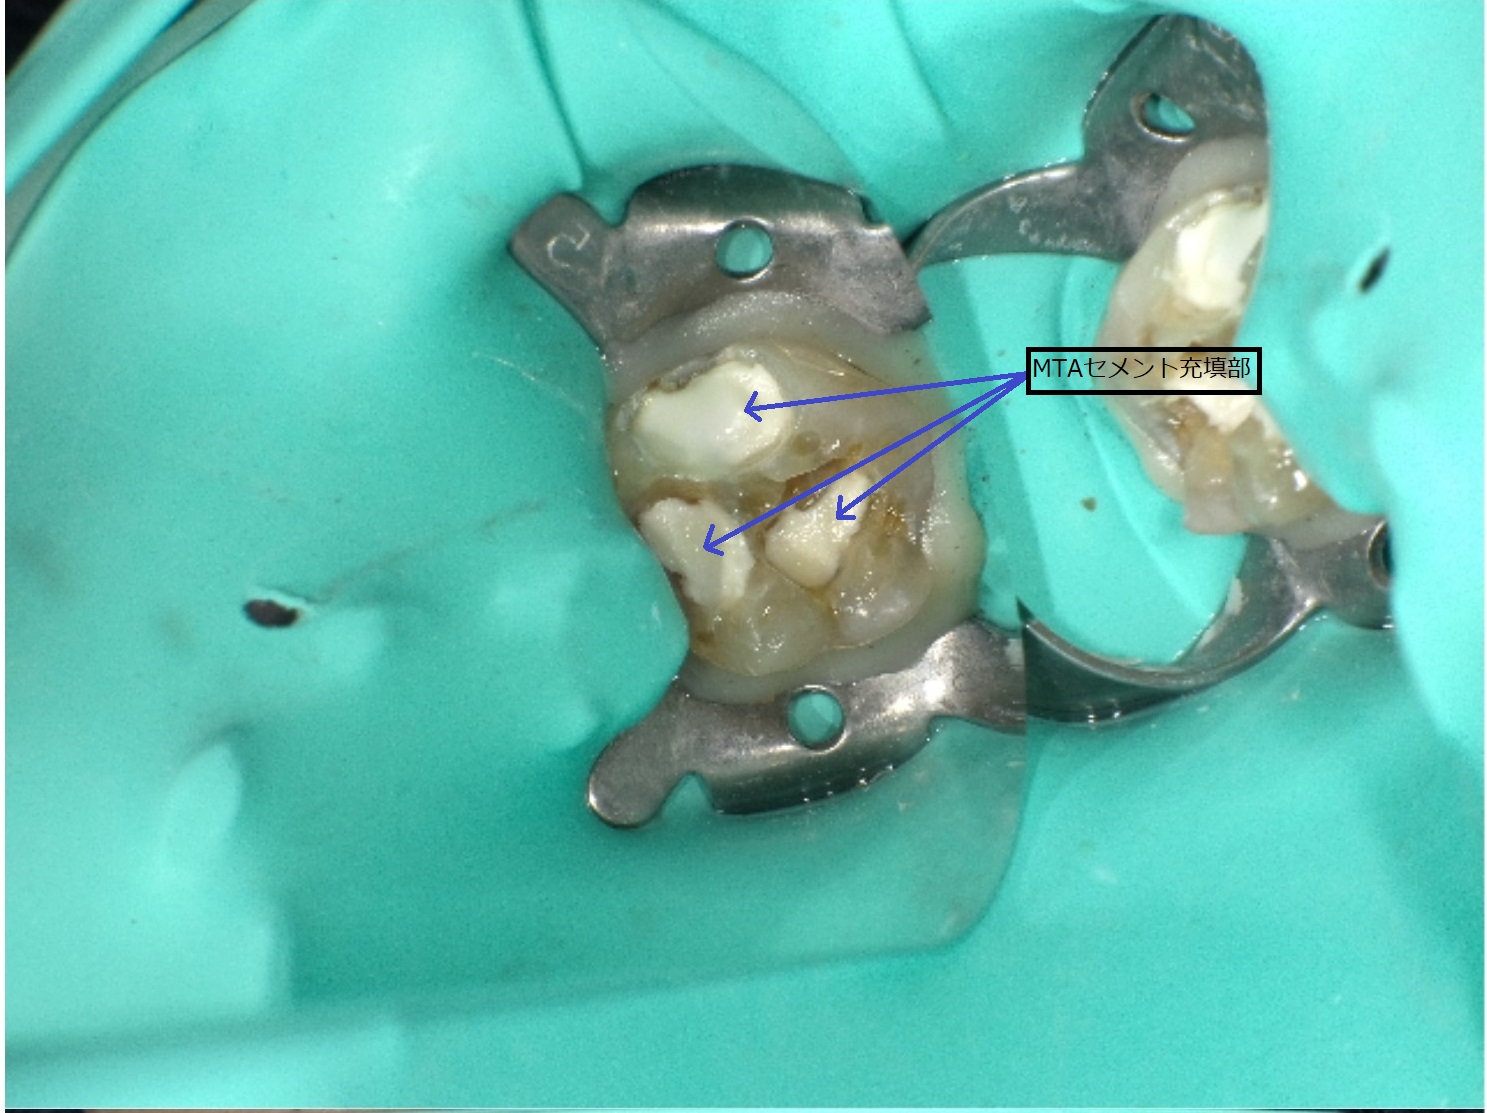

これを防ぐ治療がMTA歯髄温存療法になります。

MTA歯髄温存療法は、MTAセメントという強い消毒・鎮痛作用を持つ薬剤を用います。この薬剤で外界からの刺激を遮断し、更にはカルシウムを放出して神経の内部にも自分の体由来の壁をつくる性質を利用して歯の神経を守ります。処置後は別に詰めもの・被せものを行い、歯を多重に防護して二次う蝕の防止に努めます。

MTAの治療はラバーダム(感染防止ゴム)、消毒用レーザーによる感染対策、そしてマイクロスコープや拡大鏡による精密治療が非常に重要となります。